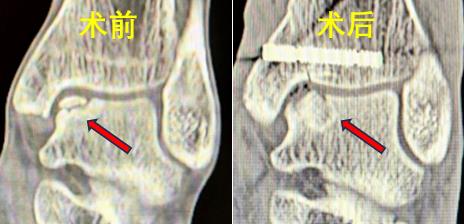

38岁的男性患者蒋某与43岁女性患者潘某,均因踝关节扭伤导致距骨软骨损伤,接受保守治疗后效果不佳,疼痛反复,严重影响日常生活。中南大学湘雅三医院骨科足踝外科团队接诊后,通过详细问诊、体查及影像学检查,明确诊断为 “距骨骨软骨损伤(Hepple III型及V型)”。

张克祥副主任医师介绍,在日常生活中,“崴脚”,即踝关节扭伤,是导致距骨软骨损伤的常见原因,但由于软骨自我修复能力较差,所以软骨损伤是公认的治疗难题。针对患者病情,团队经过讨论,决定采用自体骨膜 - 骨栓移植技术修复损伤区,同时为其定制3D打印导板,以实现精准截骨,缩短手术时间、减少副损伤。

手术当日,在麻醉科团队的密切配合下,张克祥副主任医师带领手术团队先通过关节镜彻底清理踝关节内增生滑膜及疤痕组织,再使用3D打印导板于内踝截骨,显露软骨损伤区并彻底清理病灶组织;随后,从患者自身髂骨提取带骨膜的骨栓,将其植入距骨软骨损伤处,整个手术过程顺利,患者术中生命体征平稳。术后,在张文秀、喻俊护士长所带领团队的精细化理疗与康复指导下,患者踝关节疼痛症状显著缓解,目前已逐步进行功能锻炼,患者对治疗效果非常满意。